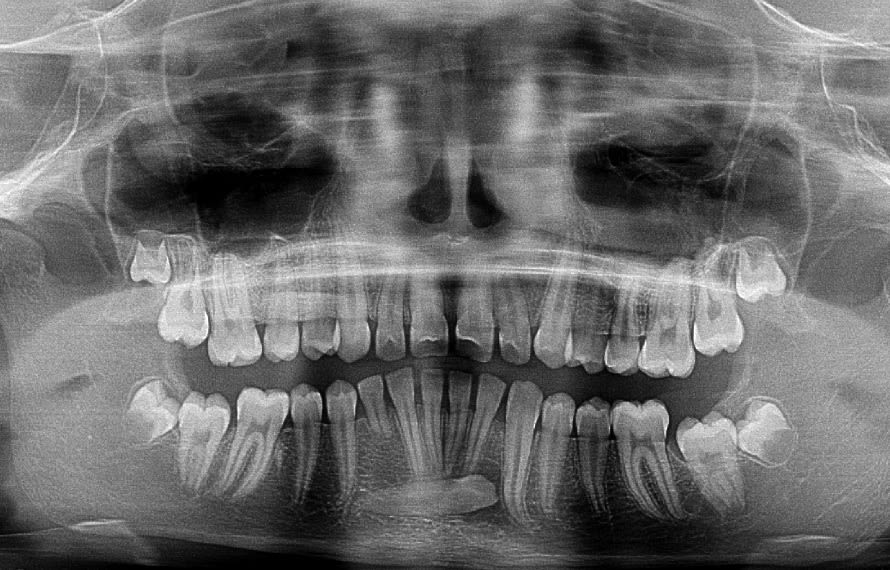

L'apex de la 43 est en bonne position, ce qui veut dire que tu n'a qu'a faire un mouvement de tipping pour redresser la dent.

Plus d'un ans pour en arriver là.

Voici un exemple de traction de canine incluse inférieure. Il faut absolument laisser les incisives inférieures totalement libres pour qu'elles puissent un peu se déplacer spontanément si nécessaire.

La supériorité du CT8 sur n'importe quel autre ancrage pour tracter les canines incluses tient en particulier à sa longueur qui permet des forces légères (25g), avec une grande amplitude de mouvement en direction contrôlée. Prévois bien un retour du fil suffisamment long après sa pliure au niveau de la ligature pour avoir de la marge. Tu pourras alors le déplier et le replier différemment en cours de traitement si tu veux, un moment donné, modifier la direction de la force. On a en effet toujours tendance à le couper trop court.

Ca y est 8 mois plus tard j'ai put poser un bracket dessus :-) .

Sur ce cas très honnêtement je n'avais pas imaginer que redresser cette canine prendrait si longtemps. Mécaniquement très simple du à la bonne position de l'apex, simple mouvement de tipping mais putain 2 ans ...